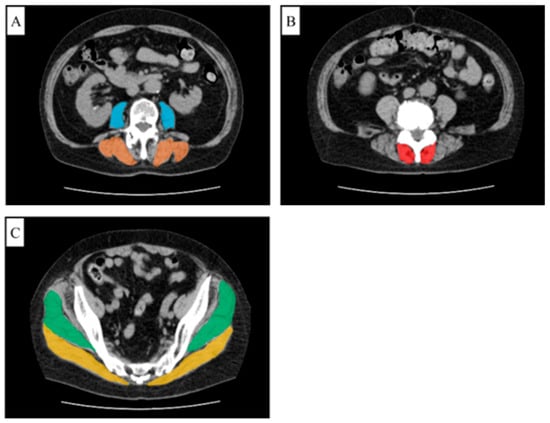

2.3. Functional Cross-Sectional Area (FCSA)